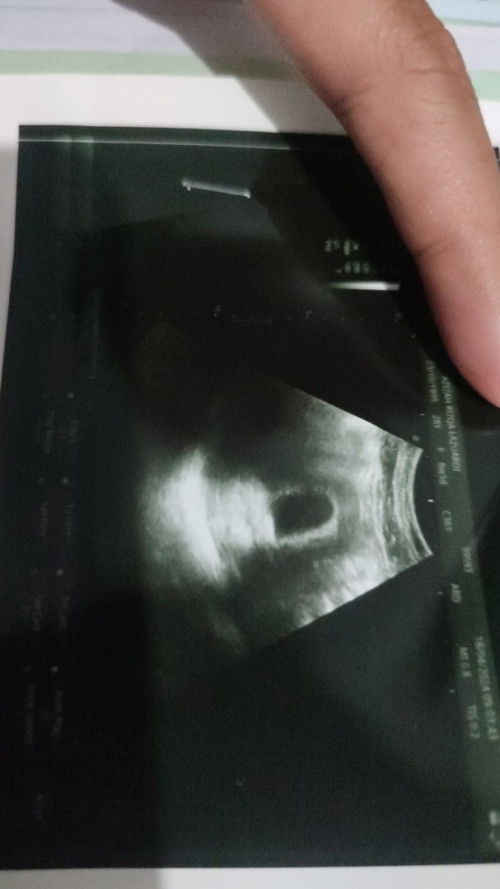

td pertamakalinya usg usia 8weeks tp hanya kantong.

riwayat keguguran tahun lalu, skrg alhamdulillah hamil lg usia 8weeks tp td pertamakali usg dan belum keliatan janinnya. disuruh 2minggu lg usg, klo msh belum keliatan disuruh kuret 💔 sedih banget ya.. #Sharing_dong_Bund #firstmom